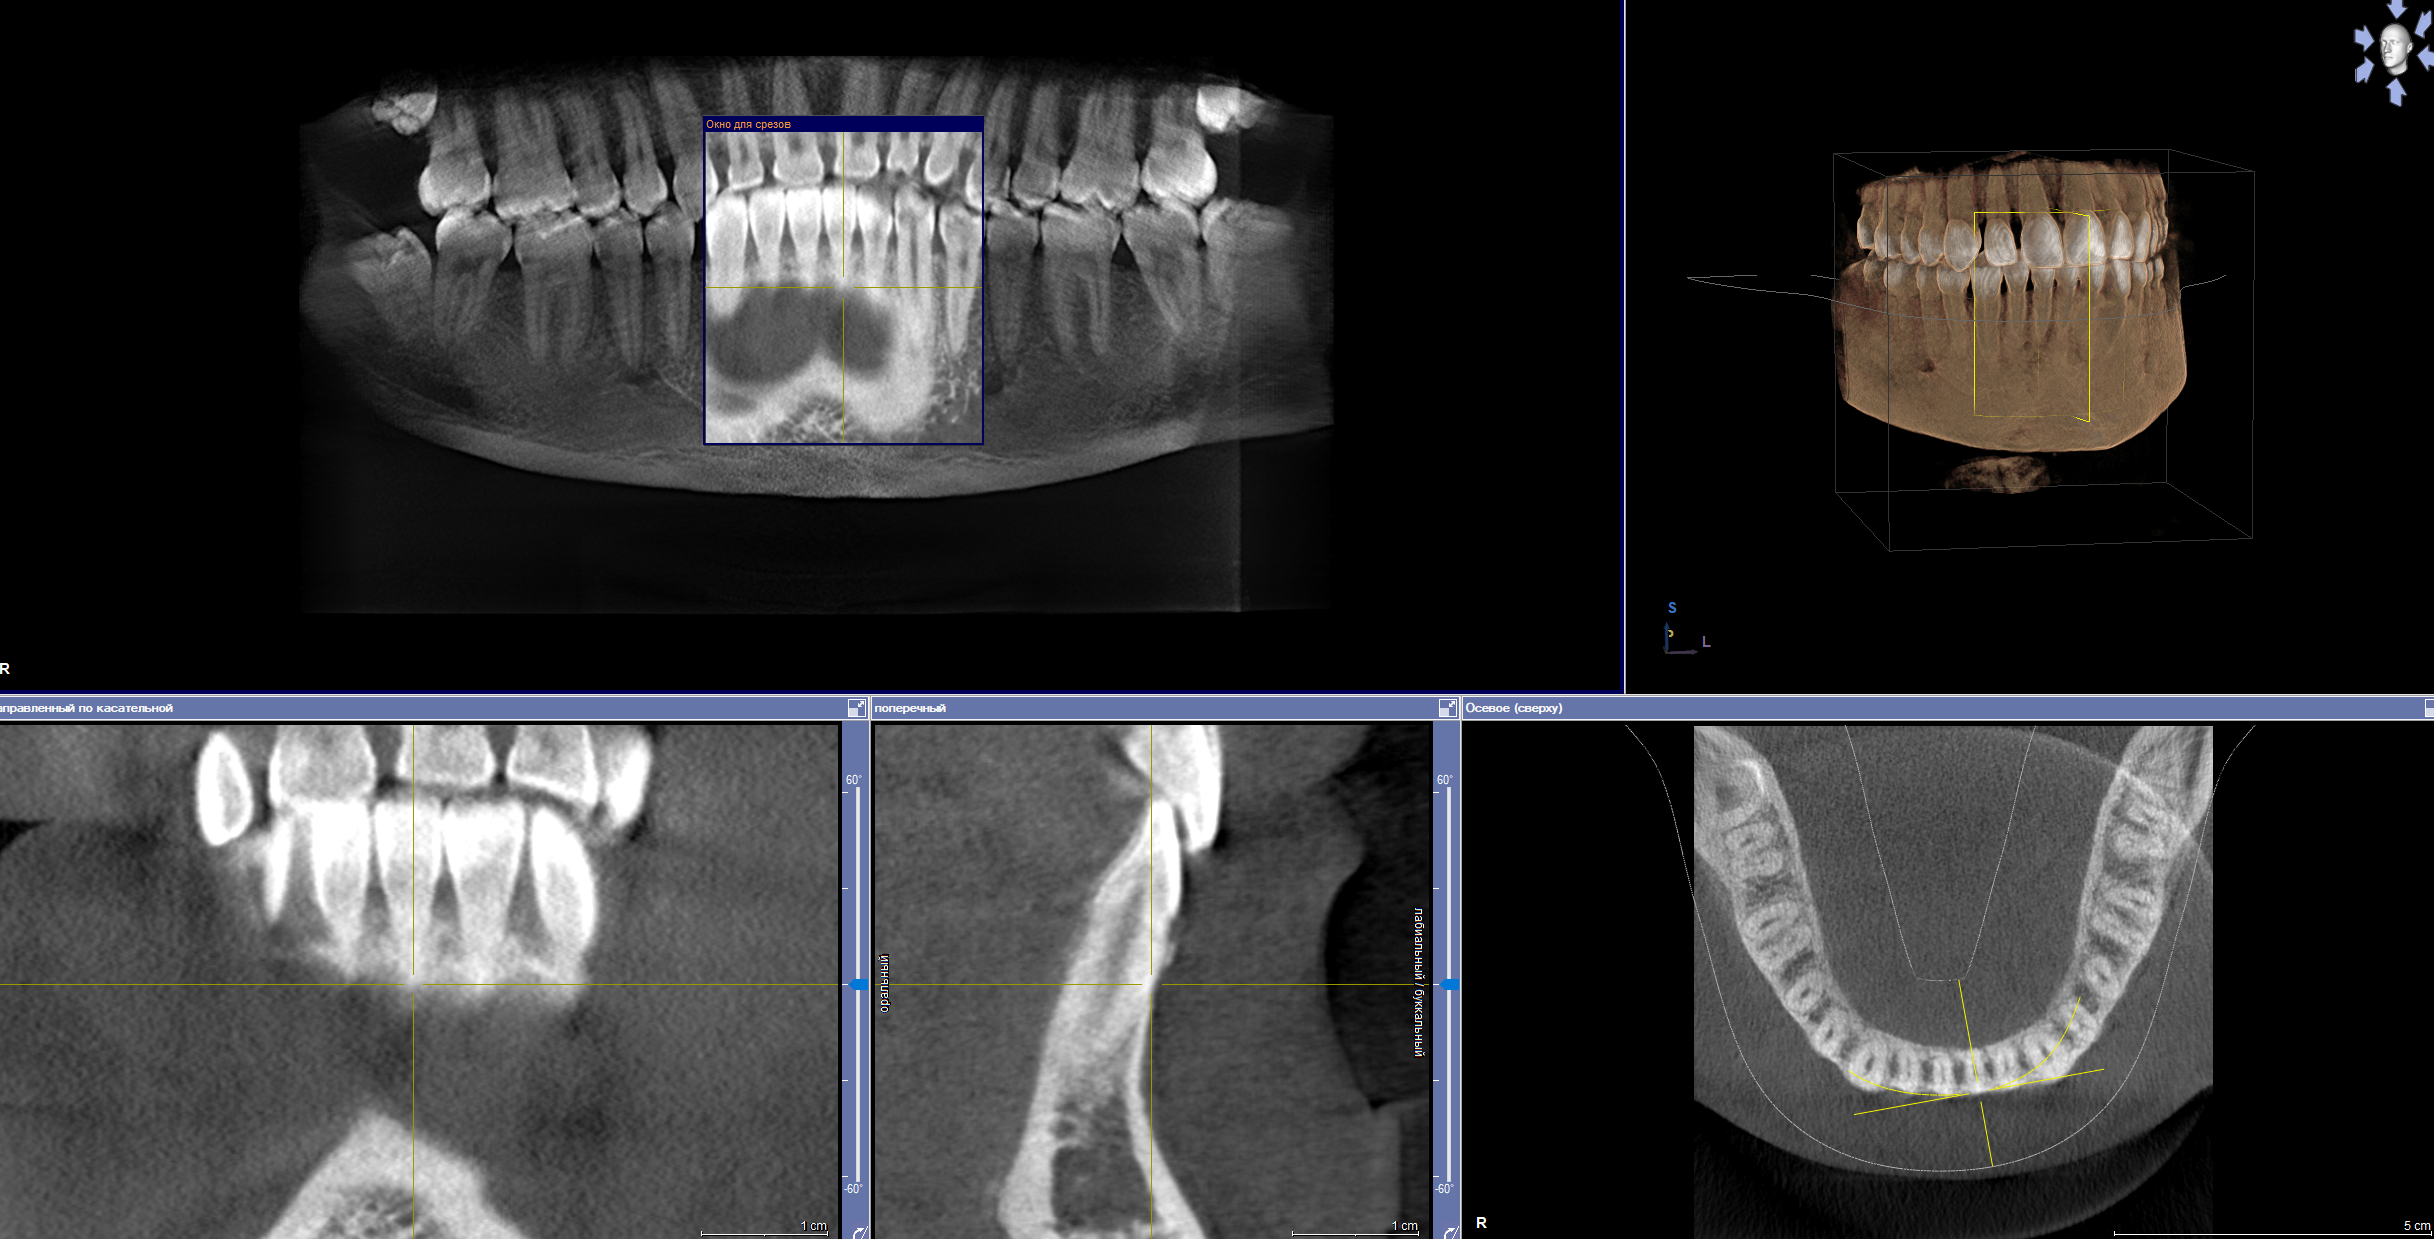

2323.jpg 238Кб, 1412x2047

1412x2047

Аноны, добрый вечер.

Посоветуйте пасту зубную после пломбирования и чистки от камня передних зубов.

Спасибо.

Аноним 06/08/25 Срд 05:38:29 1634925 25

Ска, весь рот в гное, будто бы стоматит, сходил к зубным феям - сказали все збс с корнями зубов и ни одного намёка на кариес где-либо, хотя начиналось всё будто бы флюс и самый пиздец около одного зуба, прописали онли антибиотики, но самое очко , что болезненность ещё и в области мягких тканей подбородка, который и отдает в этот самый пиздец при надавливании - даже будто бы второй подбородок чуть-чуть присутствует, температура и общая слабость, есть риск флегмоны? пиздец за шо(

Аноним 06/08/25 Срд 10:08:53 1634947 26

Как профиль лица меняется после удаления восьмерок? В инете нашел только фотки до/после у женщин, и вроде как челюга уменьшается. У мужиков так же? После удаления не получится больше моггать челюхой омежек?

Аноним 07/08/25 Чтв 13:36:06 1635134 27

>>1634947

>Как профиль лица меняется после удаления восьмерок